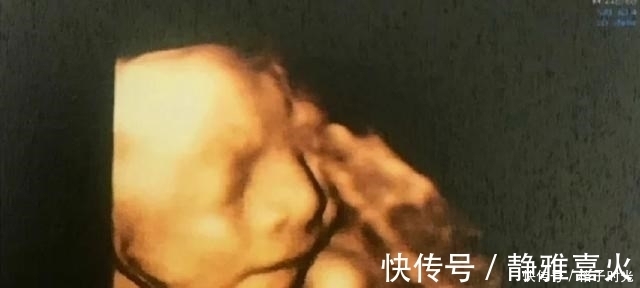

肚子里的胎儿有“七大怕事”,准妈妈不要再做了,以免伤身又伤娃哦~